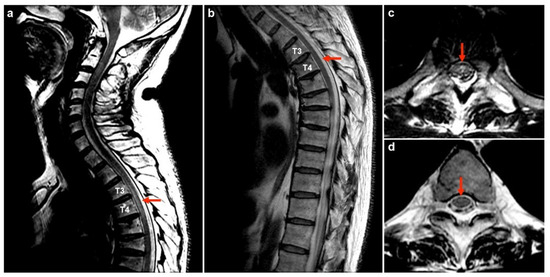

| 1 | 50M/chronic HBV | 1st AZ a/13 | MOGAD | − | + | 175 | 99 | 0 | 78.1 | 0.47 | NA | Bil thalami, pu, subcortical WM, brainstem | T3–T4 | PT | R | Index case |